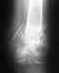

Re: Интрамндуллярный металлоостеосинтез бедра дистальным бедренным штифтом

Ходить с тростью с каждым днем получается все лучше. И в плане равновессия моего, и в плане колена. Но дальше квартиры пока боюсь. Уже колено болит меньше, но полную нагрузку пока не выдержит. А вот на корточки сесть не получиться. К 8 неделе уже нога дальше чем на 90 градусов не сгибалась. Если пытаться и дальше согнуть - появляются боли в самом конце бедра в районе колена. Там еще через кожу можно нащупать заостренный конец болта. Сначала думал на этот болт, но в больнице сказали, что раньше чем через год об этом разговора быть не может. Так что пока разрабатываю колено, может и лучше будет... Выложил опять снимок, там болты лучше видно. Скажите, это нормально болт установлен?